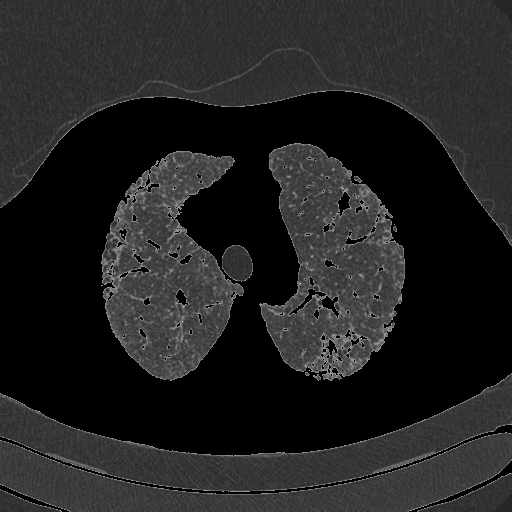

我在图像1上使用阈值掩码(图2)创建了以下图像(图3)。我试图使用opencv将图像3(肺)中央图像之外的所有像素转换为一种颜色(例如黑色)。基本上,这样我就只能在一个均匀的背景下(甚至是透明的)看到肺部的图像。我的问题是外部像素和图像3中肺内像素的相似性。这能用opencv吗?

编辑:最后一次note...here你的阈值已经移除了肺的一些部分。我在肺内的阈值中加入了一些洞,但这遗漏了一些被移除的边界上的块。如果你在面具上做轮廓检测,如果它很重要的话,你实际上也可以平滑一些。查看OpenCV的轮廓特征教程上的“等高线近似”一节。基本上,它将试图平滑轮廓,但坚持在一定的epsilon距离的实际轮廓。这可能很有用,而且很容易实现,所以我想我会把它作为一个建议放在这里。